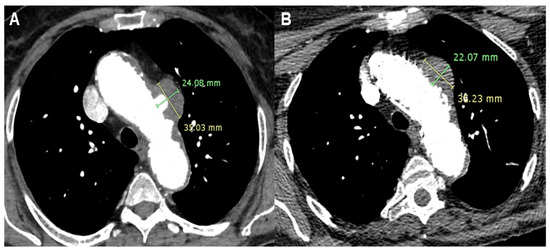

A 78-year-old gentleman underwent TEVAR in 2002 for a post-traumatic saccular pseudoaneurysm. In April 2021, he was diagnosed with severe aortic valve stenosis. He underwent an electrocardiogram (ECG)-gated CT study to plan a trans-apical aortic valve implant, which also revealed a perfused, ulcerated plaque outside the endoprosthesis consistent with a type IB endoleak. We prioritized aortic valve implantation and planned follow-up CTA of the thoracic aorta after the aortic valve treatment [10]. Postoperatively, during cardiological rehabilitation, the patient contracted SARS-CoV-2, which required hospitalization and a prolonged stay in the ICU. Two months after surgery, another ECG-gated CT was performed due to a suspected left auricle thrombus during hospitalization. The scan revealed a completely new scenario with post-isthmic aneurysmal dilatation and a large type III endoleak (65 mm) with a thick eccentric thrombotic flap. There was also posterior expansion causing erosion of the lateral walls of C5 and C7.

A few days later, a TEVAR was performed (Terumo Relay Pro 34-34-200 mm) with the proximal landing just after the origin of the left subclavian artery. Follow-up CTA showed a reduction in the axial diameter of the aneurysm (61 mm vs. 65 mm) and a marked reduction in the previously observed endoleak phenomena. The postoperative course was uneventful, with the patient’s ICU stay lasting one day and discharge occurring six days after the procedure.

Three months following TEVAR, the patient developed oral bleeding. Fibro-laryngoscopy revealed diffuse mucous varicose veins in the nose and at the base of the tongue. Surgery was performed to cauterize the varicose veins at the tongue base. Follow-up CTA showed an increase in the diameter of the excluded aneurysm with the appearance of type II endoleaks, as well as some periprosthetic air traces and suspected aorto-bronchial fistula (Figure 5). Given the clinical situation, the patient was readmitted for further diagnostic evaluation. No macroscopic mucosal fistulous pathways were observed via gastroscopy or tracheobronchoscopy. Blood cultures and PET-CT were conducted, revealing periprosthetic uptake suggestive of an infectious process. Concurrently, likely due to antibiotic therapy and various diagnostic procedures, the patient developed acute renal failure, ultimately requiring dialysis.

Figure 5.

Patient 5’s Computed Tomography Angiography reconstruction showing the type III endoleak caused by rupture of the TEVAR secondary to infection.